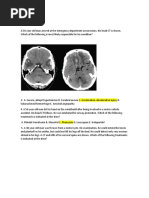

Investigation of stroke